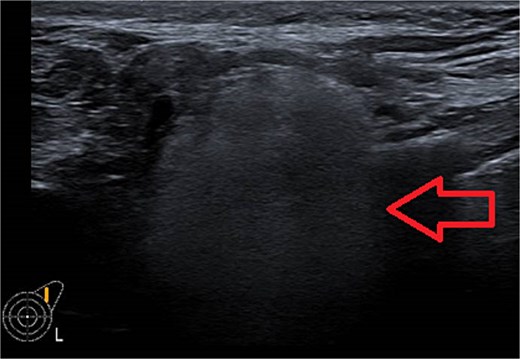

One week later, the patient reported a new lump in the left supraclavicular area. Examination revealed a 2 × 3 cm, nontender, mobile mass, confirmed by ultrasound to be silicone deposition (Figs 3 and 4). Increased breast swelling and lymphadenopathy were attributed to implant rupture and silicone migration.

Typical snowstorm appearance of supraclavicular silicone lymphadenopathy.

Imaging is a vital first step in the diagnostic evaluation of patients with lymphadenopathy. Ultrasound is the primary tool for diagnosing silicone lymphadenopathy, while additional imaging techniques, including MRI, CT, and mammography, can offer further insights for confirmation and detailed assessment of lymphadenopathy [11]. The sensitivity and specificity of using ultrasound to diagnose silicone lymphadenopathy by identifying the snowstorm sign have been reported as 87.5% and 100%, respectively [11]. In our case, the ultrasound typical snowstorm appearance was enough to make the diagnosis. Even though if any clinical concern about malignant or infectious process, cytological or histological evaluation is mandatory to confirm the diagnosis. Also in patients with previously treated breast cancer and having the implant as reconstructive measure; concerns about disease recurrence should be carefully considered.